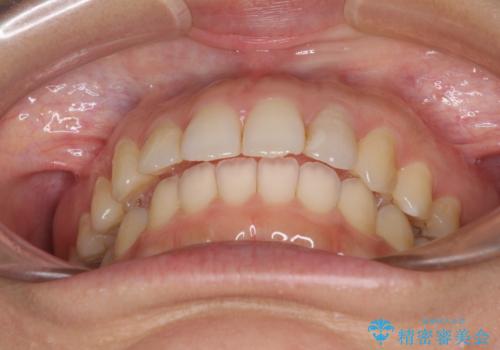

インビザライン矯正で前歯のデコボコを改善

骨格的に下顎骨が左にずれており、上下の正中一致は困難ではありましたが、IPR(歯と歯の間を削る)や後方への移動など組み合わせて、できる限り改善しました。

インビザラインはマウスピースを外している時間が長いと、長期間使用しても前歯のデコボコはあまり改善されません。こちらの患者様は治療期間が長くなり、装着時間が短くなってしまったことで、気になる部分の改善により長期間を要するようになってしまいました。